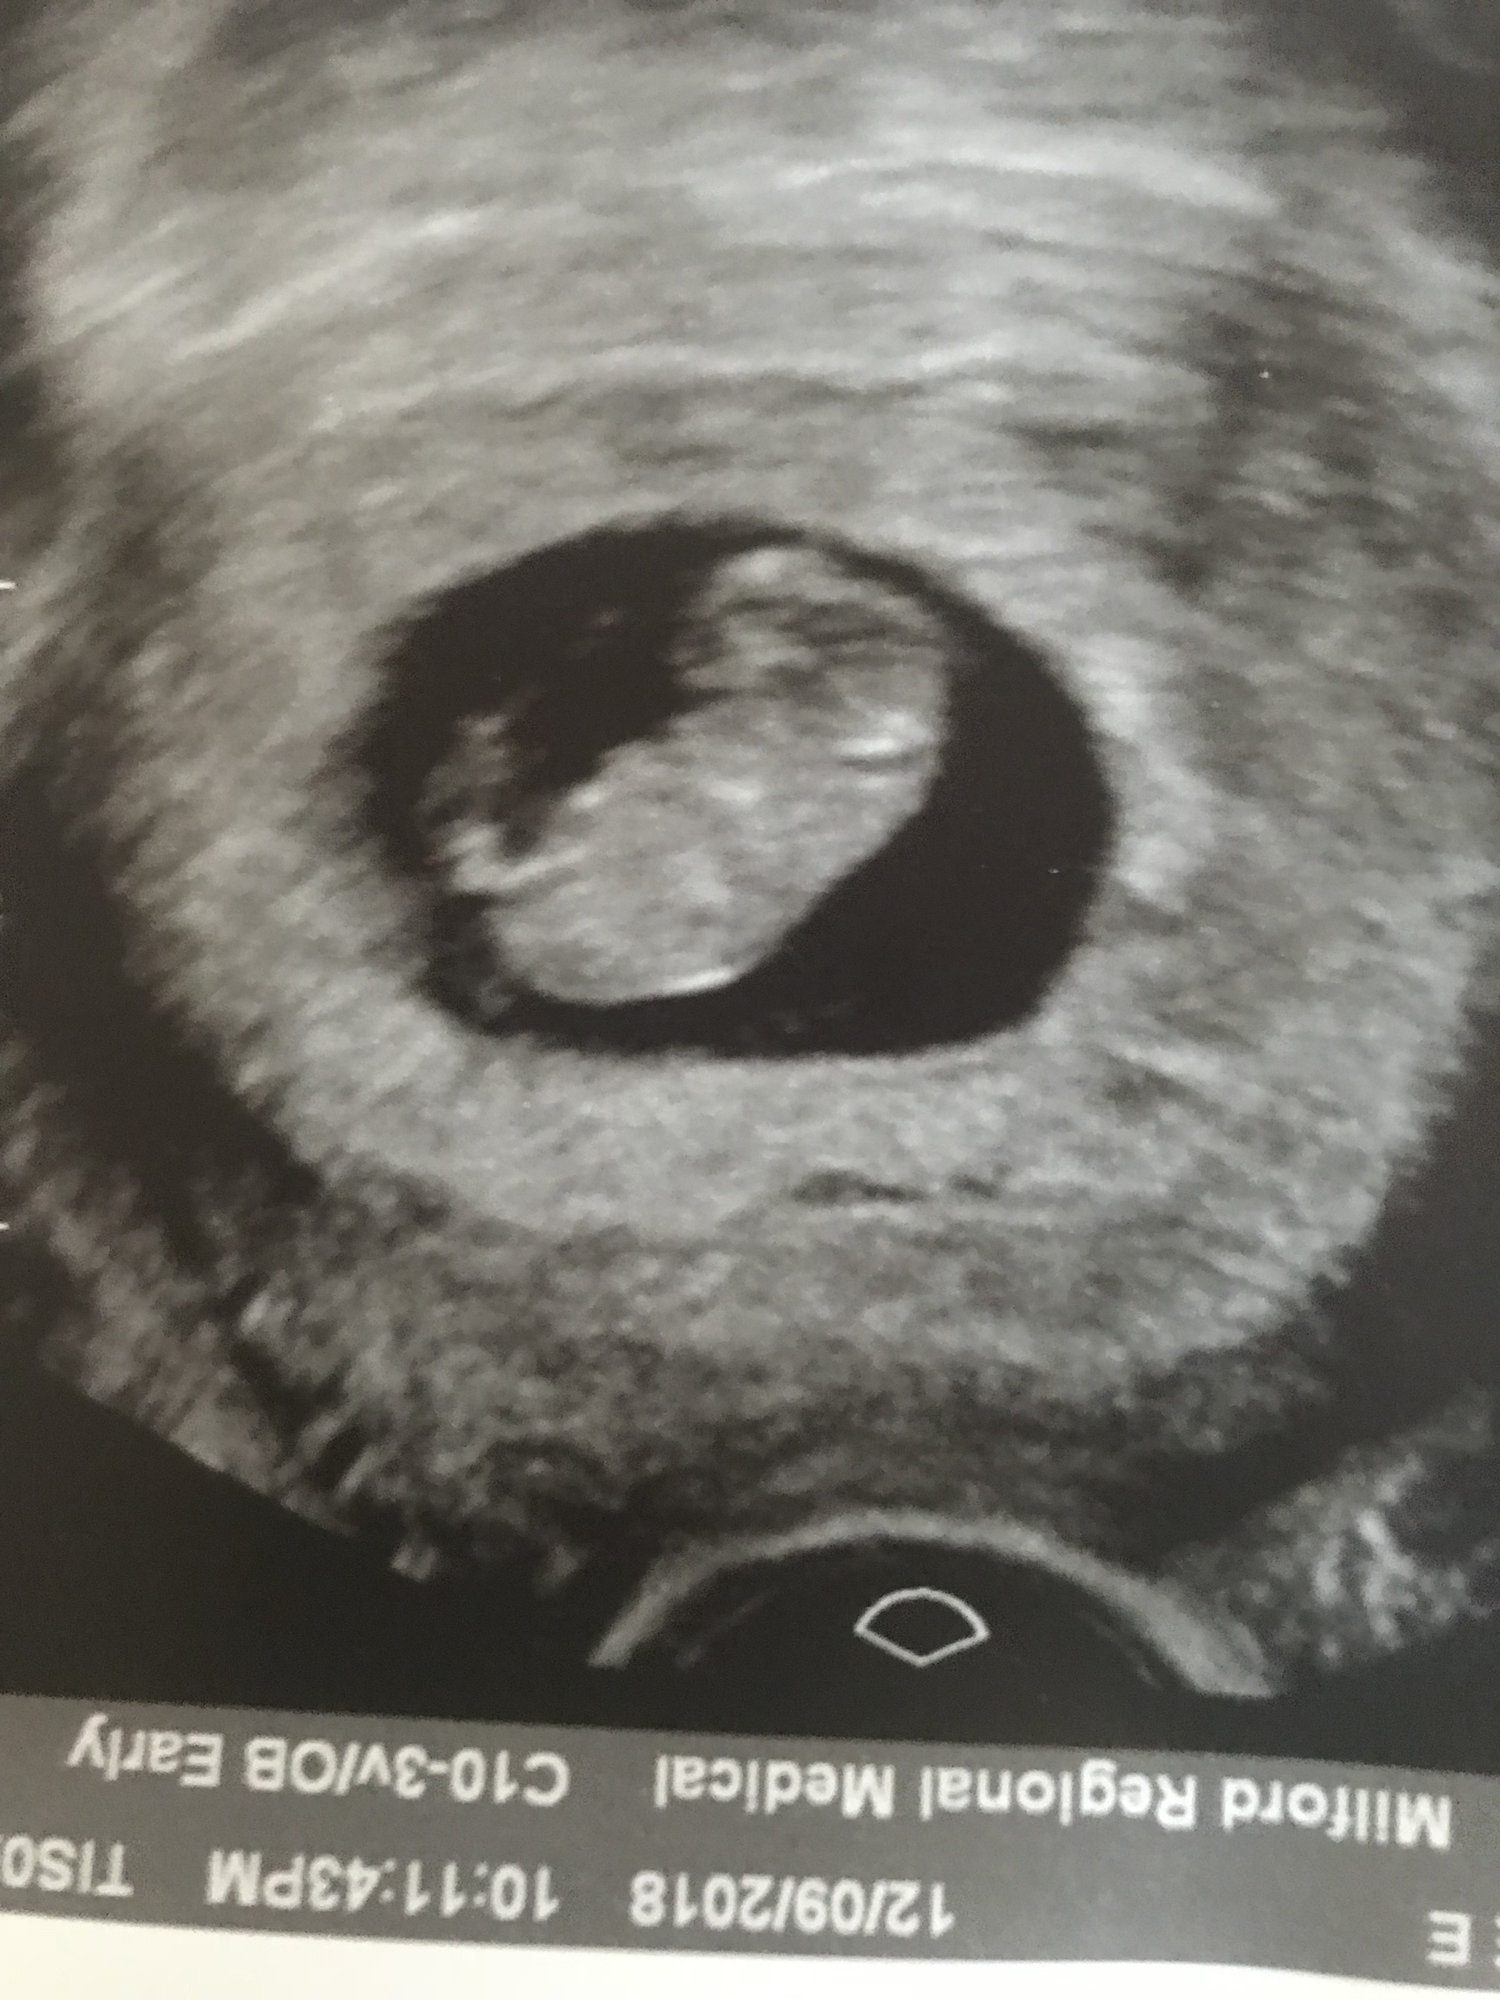

Second ultrasound! I’m 9 weeks today and baby is measuring 8wks 4 days. Within the margin so they’re keeping my 7/11 due date. Strong heartbeat at 178!